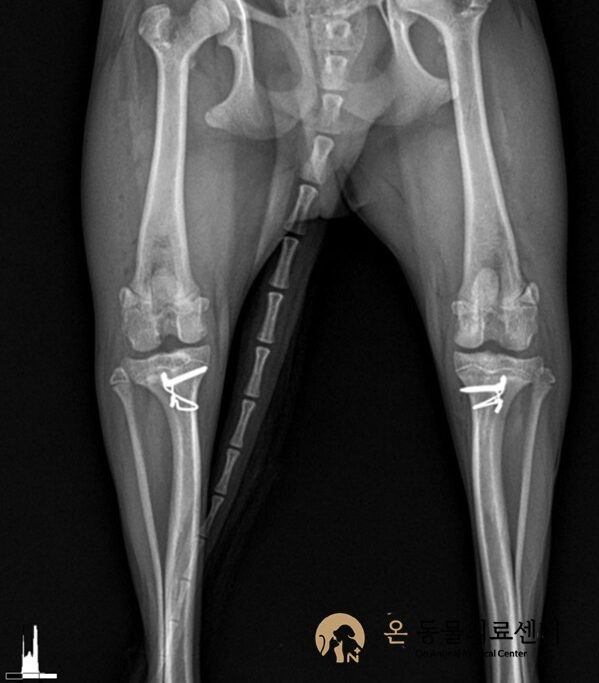

슬개골 탈구 수술은 정확한 진단과 수술 환경이 결과를 좌우합니다.

본원은 정형외과 수술을 고려한 장비와 시스템을 갖추고 있으며,

수술 전·후 방사선 검사를 통해 관절 정렬과 수술 결과를 객관적으로 평가합니다.